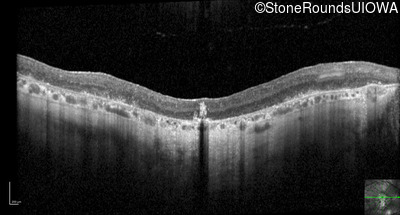

Optical Coherence Tomography - Right - 1/200 sc

Exemplar / OCT Stack

OCT Stack